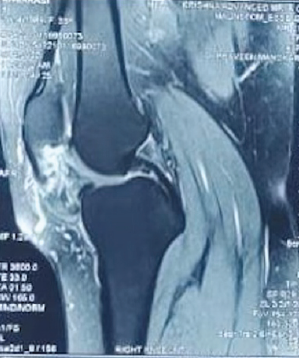

Distal Femur Extension Osteotomy for Fixed Flexion Deformity Following Distal Femur Malunion – A Case Report